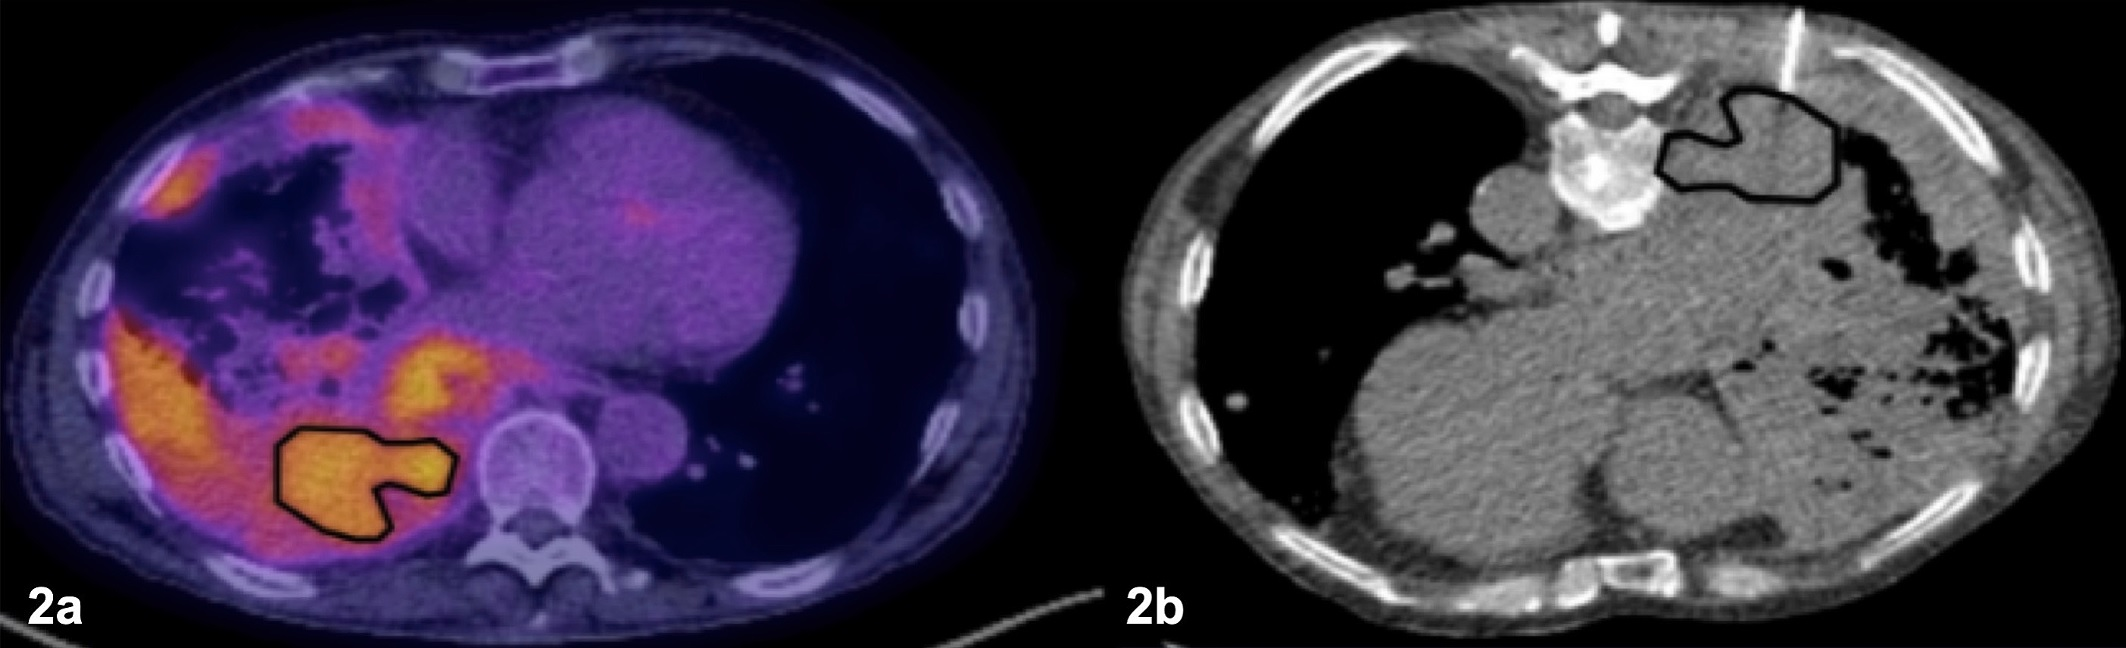

Remnant lung recurrence after percutaneous transthoracic needle biopsy (PTNB) following wedge resection. (A) Preoperative contrast-enhanced axial CT scan in a 76-year-old male patient shows a 1.8-cm solid nodule in the left upper lobe (arrow). (B) The patient underwent PTNB for nodule diagnosis. A nonenhanced axial CT scan showed that the introducer needle (arrowheads) was inserted into the inner portion of the nodule (arrow), traversing the lung parenchyma. The diagnosis on the basis of results from the PTNB was adenocarcinoma, and the patient subsequently underwent left upper lobe wedge resection 7 days after PTNB was performed. The final diagnosis was adenocarcinoma of the solid-predominant type, pT1bN0. (C) At postoperative follow-up, a nodular opacity emerged adjacent to the surgical site (arrowheads) and increased in size at subsequent imaging. This soft-tissue lesion was confirmed at PTNB as metastatic adenocarcinoma, and the patient underwent salvage radiation to treat the remnant lung recurrence.RSNA